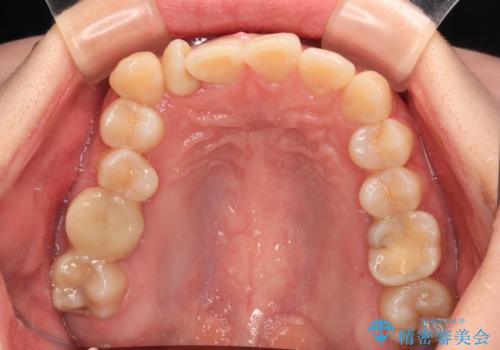

捻転の強い前歯 ワイヤー装置での非抜歯矯正

- 前歯のデコボコ、特に90度捻れている上顎前歯を気にして来院された患者様です。

マウスピースでもワイヤーでも対応可能でしたら、捻転が非常に強いことから、患者様と相談の上ワイヤー装置にて矯正治療を行うこととしました。

捻転を解消する際に、歯列全体が前方に突出して出っ歯の仕上がりとなることが懸念されたため、補助装置を用いて上顎歯列全体を後方に移動する力をかけることとしました。

当初予定通り1年半ほどの治療期間で、非常に綺麗な歯列に仕上げることができました。